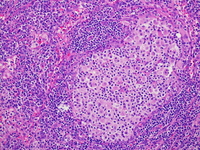

Lymph node; H&E; 20X objective.

The left supraclavicular lymph node demonstrates partial effacement of normal lymph node architecture by expansion of the interfollicular areas and dilated sinuses.  Few scattered small follicles with germinal centers are present.